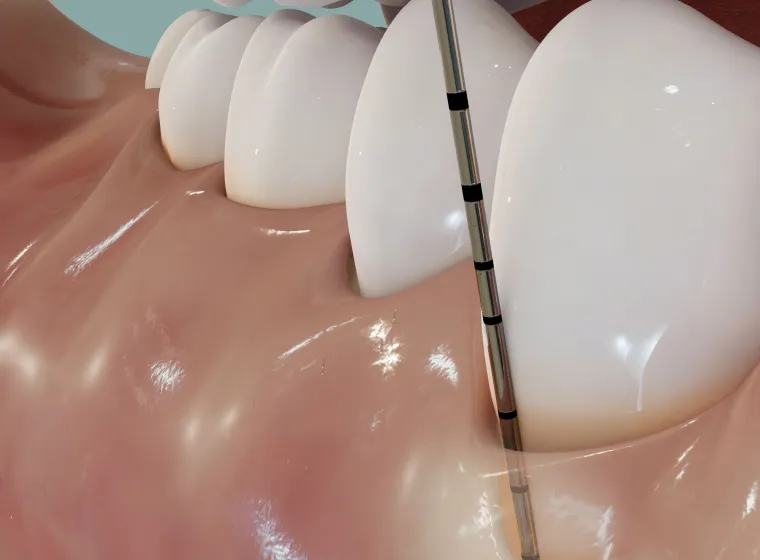

歯周ポケット検査

まず行うのが「歯周ポケット検査」です。

専用の細い器具で、歯と歯ぐきの間にあるすき間(歯周ポケット)の深さを測定し、歯ぐきの健康状態を数値で確認します。

健康な歯ぐきのポケットは2~3mm程度ですが、4mmを超えると炎症が進行している可能性が高く、6mm以上になると中等度~重度の歯周病と診断されることもあります。 -